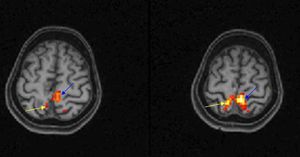

Functional magnetic resonance imaging (fMRI) provides a sensitive, non-invasive tool for mapping patterns of activation in the working human brain. The most common #fMRI technique is the blood oxygenation level dependent (#BOLD) technique. This technique measures localized changes in tissue oxygen content by alterations in the local magnetic field owing to the different magnetic properties of oxygenated (diamagnetic) and deoxygenated (paramagnetic) blood. The basic technique for a clinical fMRI scan involves acquisition of high-resolution 3 dimensional anatomic images (eg MPRAGE or T2), followed by BOLD GRE or SE EPI images showing functional activation. Current fMRI research concentrates on task-related studies and designs measuring functional connectivity. Task-related activation studies aim to characterize the neural responses to experimental conditions, which may be visualized as maps of brain activity. Figure shows axial T1-W images in neurologic format with overlaid functional activation show right foot (yellow arrow) and left foot (blue arrow) activation in the parasagittal precentral gyri. The patient was asked to curl his toes during "on task" and rest during "off task" (L.M. Shah et al, Seminars in Roentgenology 2010).